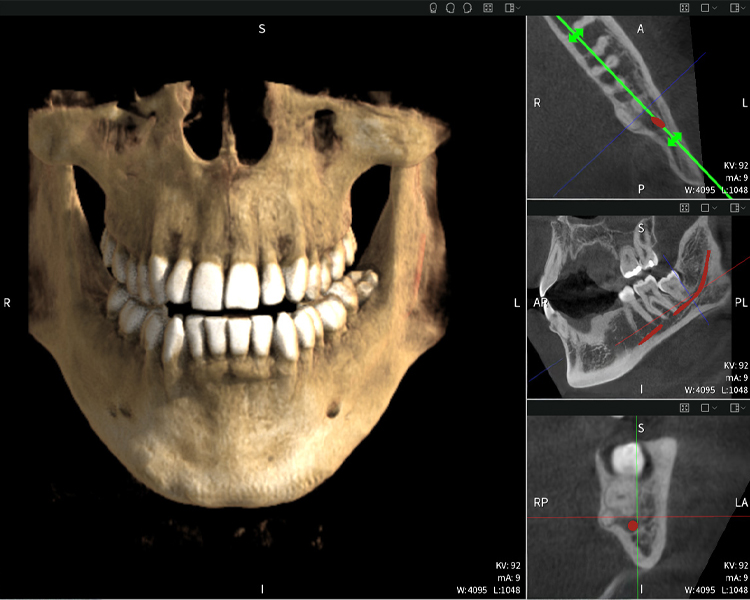

Figura b: Resultados de imagen de Seethrough Max, sobre un fondo negro.

Figura b

Las figuras b–d muestran varias vistas de una reconstrucción 3D de la mandíbula, proporcionando una visión general completa de la anatomía mandibular, la posición de los nervios en relación con los dientes y permitiendo evaluar la simetría y alineación dentaria.